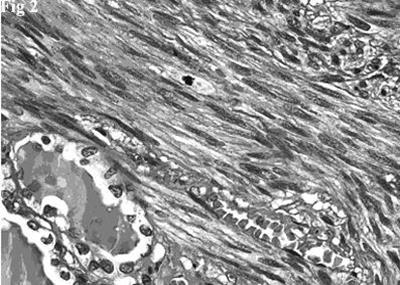

Figure 2.Hematoxylin and eosin stain showing a fascicle of spindle cells contiguous to residual thyroid follicles. The spindle cells posses blunt-ended, moderately hyperchromatic nuclei. A mitotic figure is evident (top, center).

Histologically there was a proliferation of elongated spindle-shaped cells, arranged in interweaving fascicles of varying sizes, intersected at right angles, having blunt-ended, cigar-shaped, centrally located, nuclei. Nuclear hyperchromatism and pleomorphism were generally mild and, occasionally, moderate. The cells had an abundant cytoplasm that varied tinctorially from pink to red in sections stained with hematoxylin-eosin. There was no coagulative tumor cell necrosis. Mitotic figures were easily identified (10 mitoses per 10 HPF). Rare and scattered residual thyroid follicles were surrounded and deformed by the neoplastic fascicles (Figure 2). The follicles, with central colloidal deposits, were lined by flattened or cuboidal epithelial cells.